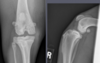

Which radiographs show an active vs. inactive pattern of periosteal reaction?

Left 2 radiographs: inactive; smooth, well defined margins

Right 2 radiographs: active; fuzzy, less sharp margins